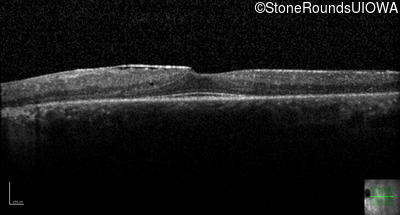

Optical Coherence Tomography - Right - 20/20 -1

Exemplar / OCT Stack

OCT Stack